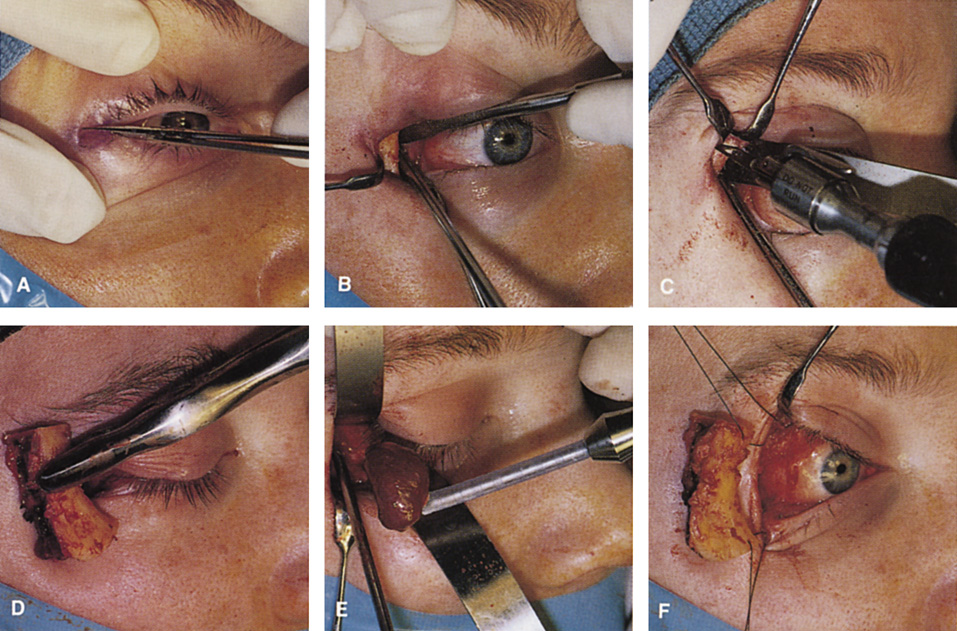

Fig. 11. A. Lateral canthotomy incision is made with straight iris scissors. B. Periosteum is elevated off of the lateral orbital rim. C. Wide undermining allows retraction of the skin incision to permit superior

and inferior osteotomies to be made with the air-driven saw. D. The bony rim has been outfractured. Because of the distensibility of the

skin, it is possible to remove a large bone flap through the small

canthotomy incision. E. The intraconal mass is extracted with the aid of the cryoprobe. F. The bone fragment is positioned for resuturing.

Fig. 11. A. Lateral canthotomy incision is made with straight iris scissors. B. Periosteum is elevated off of the lateral orbital rim. C. Wide undermining allows retraction of the skin incision to permit superior

and inferior osteotomies to be made with the air-driven saw. D. The bony rim has been outfractured. Because of the distensibility of the

skin, it is possible to remove a large bone flap through the small

canthotomy incision. E. The intraconal mass is extracted with the aid of the cryoprobe. F. The bone fragment is positioned for resuturing.

|